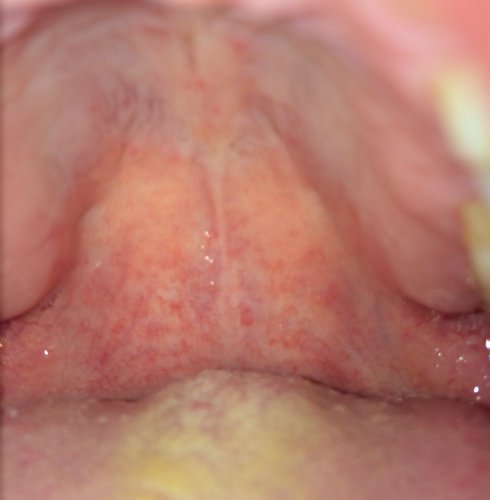

这是不是喉咙发炎上火?自己拍的,好奇怪,吞口水时只有一边疼,好一段时间了,喝板蓝根冲剂和银翘片还是

病情分析: 从描述的情况和图片看应该是咽喉炎引起的吞咽困难 指导意见: 建议患者注意休息,多饮水,多吃蔬菜水果,忌食辛辣刺激生冷寒凉食物。药物方面可以给与红霉素肠溶片、牛黄消炎片口服治疗即可